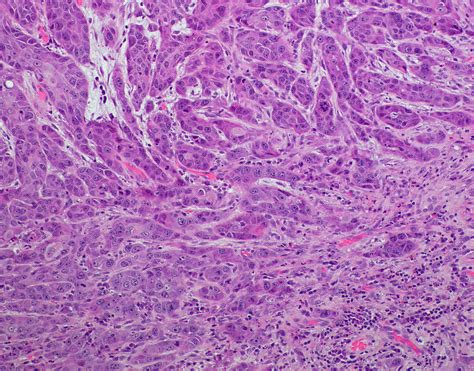

• Biopsy: A small sample of tissue is taken from the affected area and examined under a microscope.